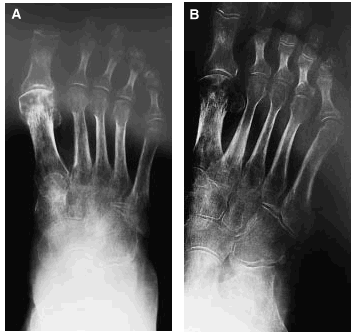

Tras 2 meses de tratamiento con ejercicios y calcitonina la enferma fue mejorando de su cuadro doloroso con desaparición del trofoedema, al tiempo que se evidencia también una regresión radiográfica de su osteopenia (figs. 4A y B).

Figs. 4A y B